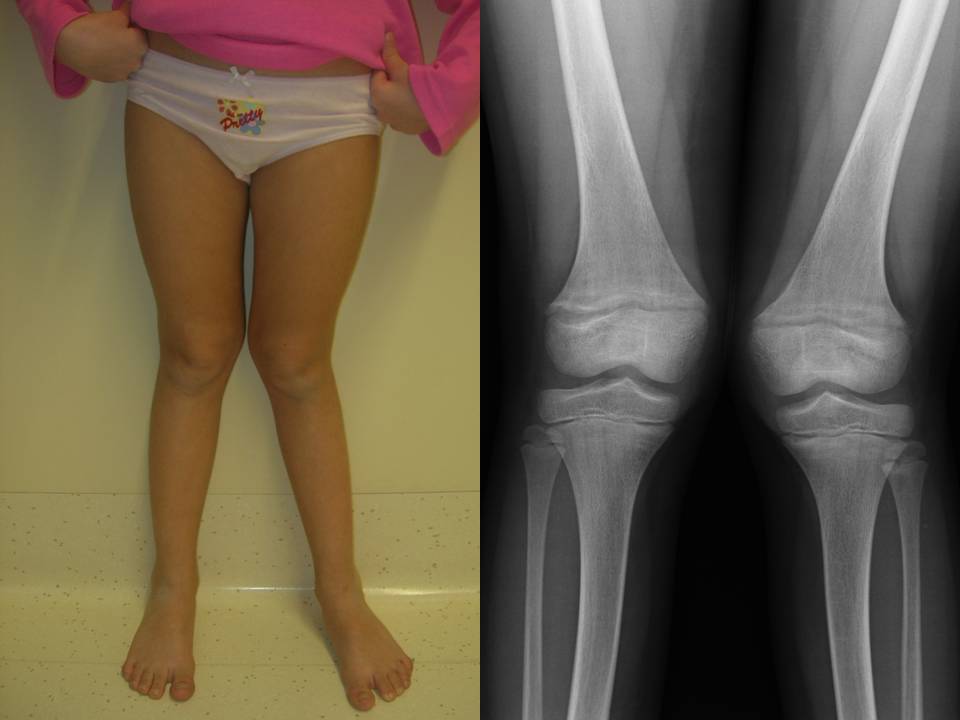

Fig. 9: rachitismo ipofosfatemico.